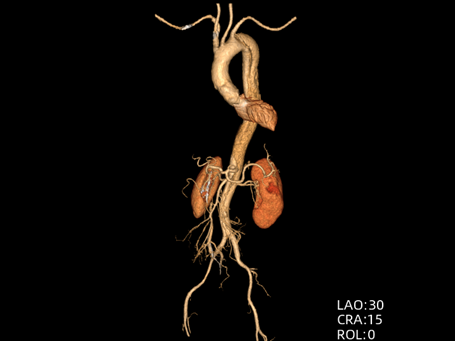

71岁男性,突发剧烈胸痛,既往有长期高血压、糖尿病病史。

时间就是生命。医生会结合症状,快速进行以下检查:医院会根据CT血管成像(CTA)进行诊断。如确诊为主动脉夹层,则会进行紧急处理,立即镇痛、控制血压和心率(如静脉注射β受体阻滞剂)。

主动脉腔内修复术:微创治疗。通过大腿根部的股动脉,将一个覆膜支架送入主动脉夹层部位,像打补丁一样覆盖住内膜破口,使血流不再进入假腔,促进假腔血栓化愈合。